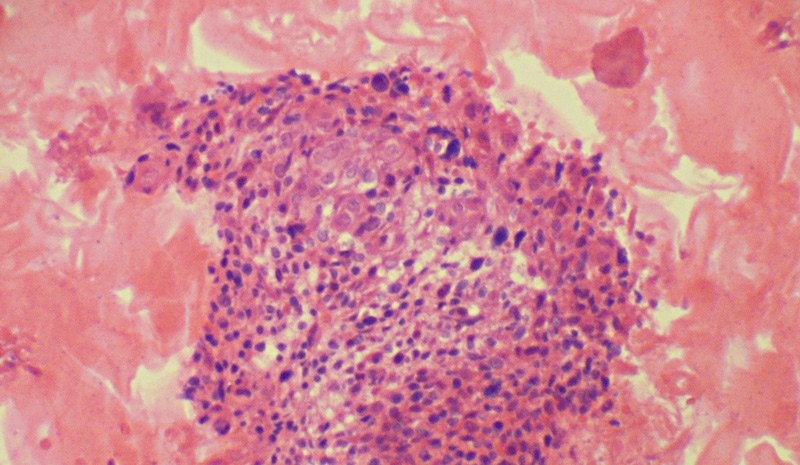

Badanie cytologiczne pozwala wykryć zmiany wywołane przez wirusa HPV, ale nie samą jego obecność. Do tego celu służy test DNA HPV. Ocenia on obecność i typ wirusa, a tym samym stopień zagrożenia rozwojem raka szyjki macicy. Pozwala więc wykryć infekcję na długo przed wystąpieniem zmian nowotworowych.